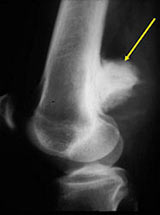

• • The work-up often consists of a physical examination, X-ray, MRI, and CT scans.

Radiographic imaging is used to help form a diagnosis. These include X-Ray, MRI, CT.